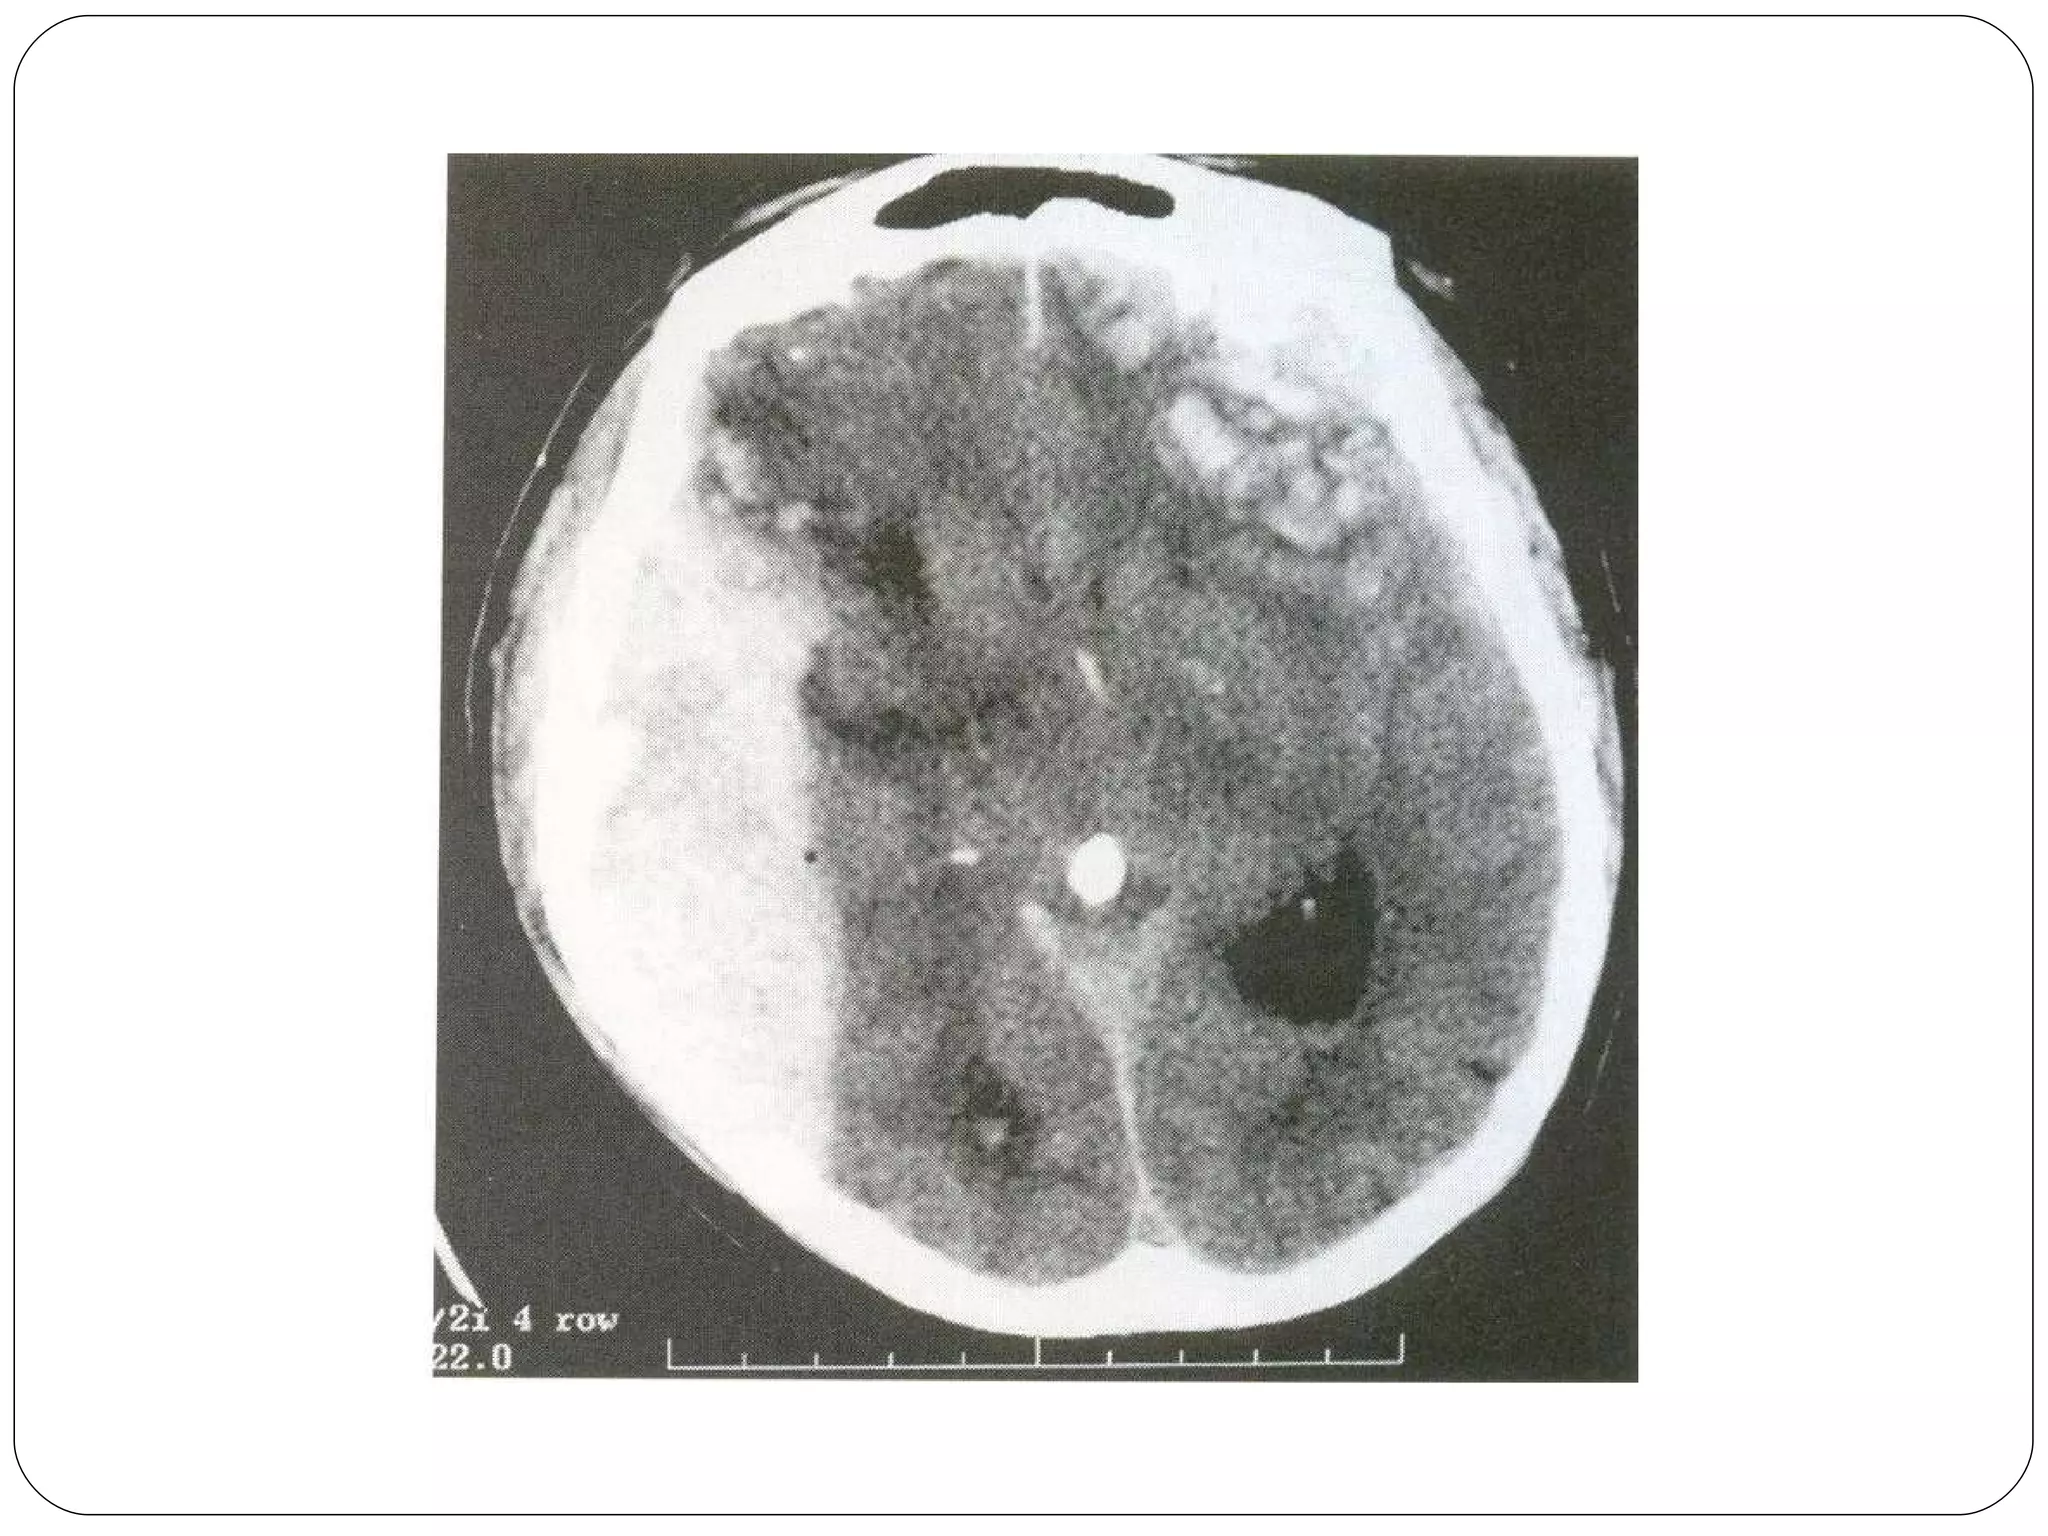

Cerebral or Extracerebral mass   Tumor Massive infraction with edema Contusion Parenchymal SDH : EDH Abscess

Cerebral or Extracerebralmass Tumor Massive infraction with edema Contusion Parenchymal SDH : EDH Abscess

TYPES OF CEREBRAL EDEMA Cytotoxic Cerebral swelling    cellular engorgement    neuron, glia  Is due to ischemia Vasogenic edema   Accumalation of extracellular fluid Defective BBB Leaky capillaries Seen in metastases, gliomas, meningiomas

TYPES OF CEREBRALEDEMA Cytotoxic Cerebral swelling  cellular engorgement  neuron, glia Is due to ischemia Vasogenic edema Accumalation of extracellular fluid Defective BBB Leaky capillaries Seen in metastases, gliomas, meningiomas

Changes in CRANIUM Sub falcine hermation  Shift of cingulate gyrus of one hemisphere under the falxcerebri to contra lateral side. Septum pellucidum may shift from midline. Uncal Herniation Tentorial – Mid brain Tonsillar – Foramen magnum

Changes in CRANIUMSub falcine hermation Shift of cingulate gyrus of one hemisphere under the falxcerebri to contra lateral side. Septum pellucidum may shift from midline. Uncal Herniation Tentorial – Mid brain Tonsillar – Foramen magnum

Investigations CT Scan with Contrast  MRI with Contrast Except cerebral abscess  Technetium brain scan – destructive skull vault, skull base lesions EEG – Cerebral abscess, focal slow waves seen Skull Film- not useful in hemispherical tumors Routine tests  Angiography, volumetric MRI Lumbarpuncture only after imaging  Biopsy

Investigations CT Scanwith Contrast MRI with Contrast Except cerebral abscess Technetium brain scan – destructive skull vault, skull base lesions EEG – Cerebral abscess, focal slow waves seen Skull Film- not useful in hemispherical tumors Routine tests Angiography, volumetric MRI Lumbarpuncture only after imaging Biopsy